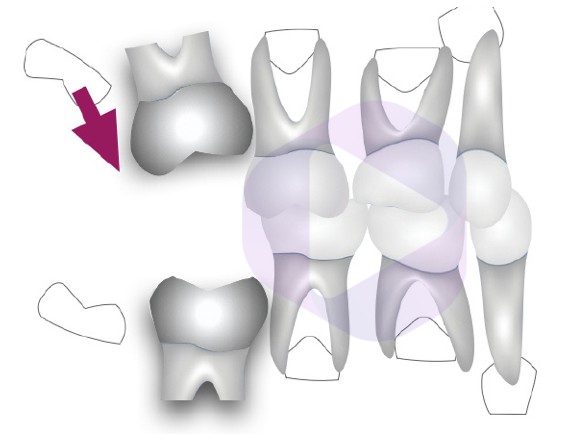

Cerca de 60% da quantidade de abertura do parafuso expansor se transfere em aumento na distância intermolares na região dentoalveolar, além de aumento do perímetro do arco, ou seja, temos mais espaço disponível no arco após a expansão maxilar rápida.

Portanto, em pacientes com relação de Classe I entre as bases ósseas, a expansão maxilar é indicada em casos de apinhamento anterior superior, corredor bucal amplo ou mesmo em pacientes com atresia maxilar transversal, com ou sem mordida cruzada posterior.

Observe na imagem acima o espaço obtido na região anterior após a expansão maxilar realizada.